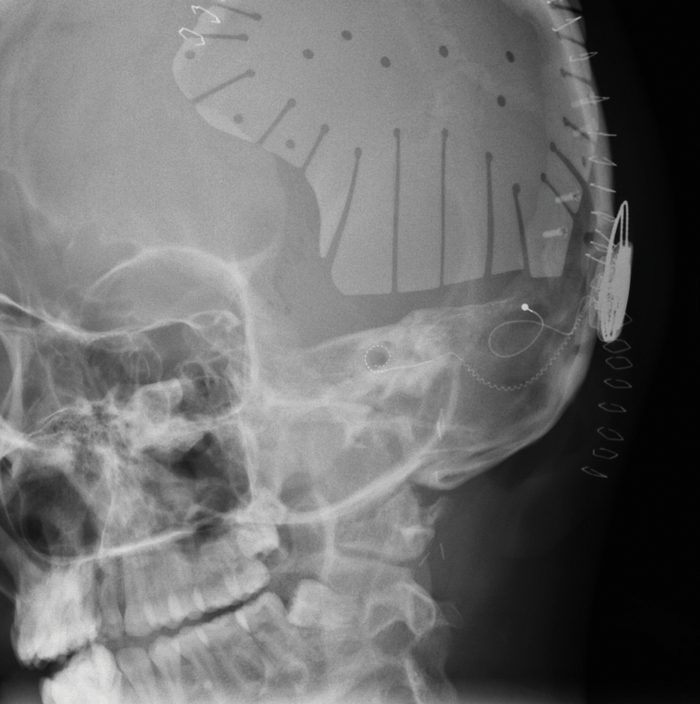

Figure I. Postoperative plain X-ray of a case of SSD secondary to trauma. Hearing in the left ear was lost as a result of a gunshot injury, contralateral hearing was normal. The patient underwent emergency decompressive craniectomy and then three months later simultaneous cranioplasy and cochlear implantation. The image shows a full insertion of the electrode and the CI body placed low, below the cranioplasty plate.